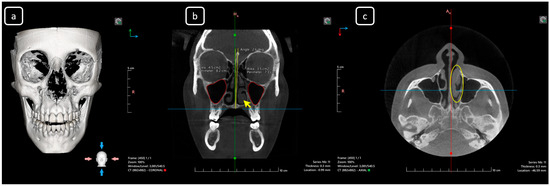

Cone beam computed tomography (CBCT) is a valuable diagnostic tool for evaluating the upper airway and maxillofacial region. This report demonstrates the clinical value of CBCT in identifying significant anatomical variations in endodontics, incidentally detected on a non-endodontic CBCT scan. A 23-year-old female patient underwent CBCT imaging at the Faculty of Dentistry-UJED to evaluate her upper airway. CBCT imaging revealed a unique, complex, and unusual anatomy of mandibular root canals, characterized by Vertucci’s type III root canals in the anterior sextant and co-occurrence of bilateral C-shaped mandibular second molars (type C2 according to Fan’s classification). No therapeutic interventions were initiated due to the patient’s asymptomatic status. CBCT imaging is a valuable tool for integrated diagnostic approaches, underscoring its role in thorough patient management. The integration of multidisciplinary interpretation of CBCT data can enhance diagnostic accuracy and optimize patient records and management, emphasizing the importance of collaborative efforts between radiologists, clinicians, and endodontists. Documenting and sharing such findings can increase awareness of rare anatomical variations, facilitating detection and contributing to medical knowledge. Full article

Figure 1